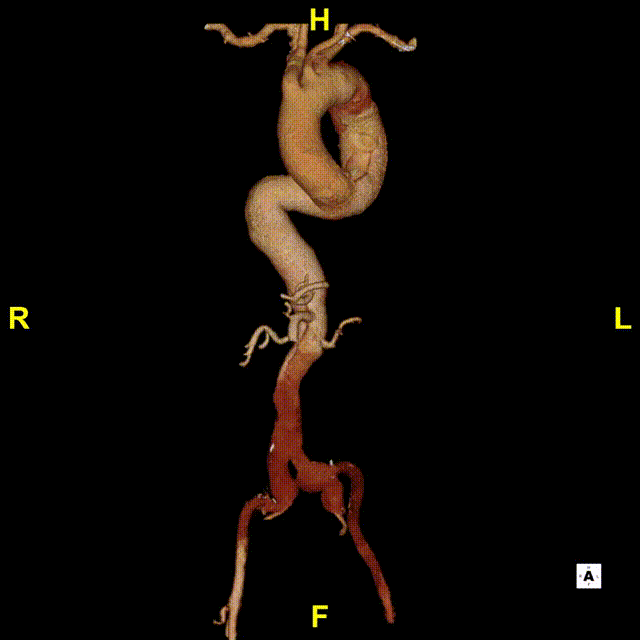

术后随访

术后随访复查,支架形态良好,真腔重塑良好,四分支及下肢血供良好。

横断面影像

3D影像